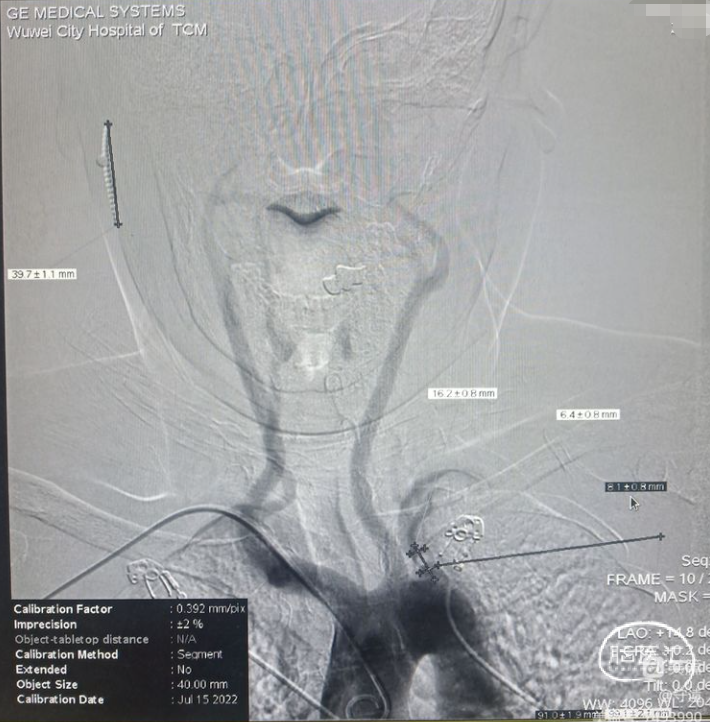

术前影像学

造影显示:左侧锁骨下动脉起始部重度狭窄。

右侧椎动脉通过基底动脉向左侧椎动脉返流供应左上肢供血,形成颅内盗血。

狭窄部位剪头所示。